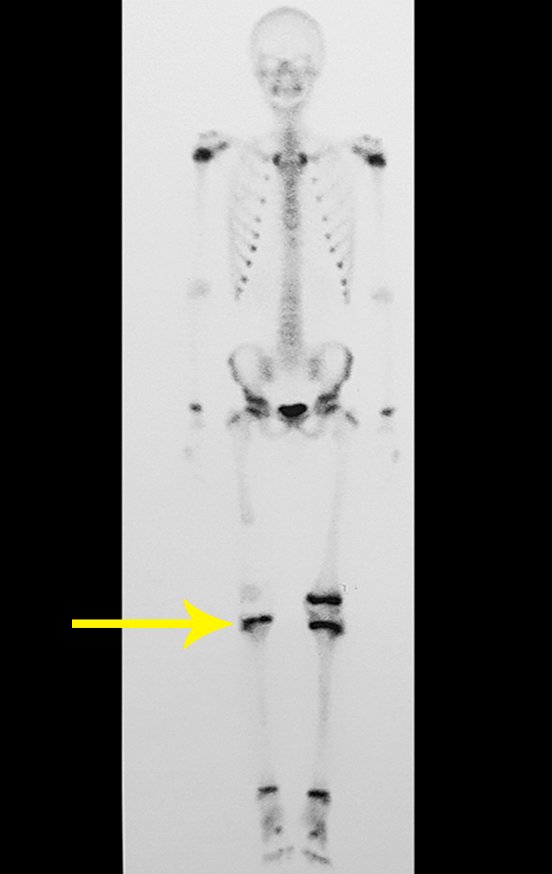

Técnica de Epifisiodese e Prótese parcial rotatória. Paciente com 11 anos de idade, apresentando dor no joelho e aumento de volume no terço inferior do fêmur direito. as radiografias de fevereiro de 2014 evidenciaram lesão produtora de tecido ósseo na metáfise, figuras 1 e 2. A cintilografia constatou tratar-se de lesão única com intensa captação na região metafisária distal do fêmur, figuras 3 e 4.